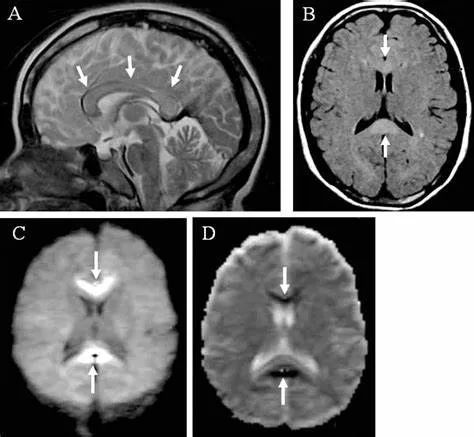

原发性胼胝体变性急性期:T2WI矢状位(A)清晰观察到弥漫胼胝体病变,FLAIR呈高信号(B),DWI呈高信号(C),ADC图呈低信号。

31岁,男性,长期饮酒,出现急性失语、短期注意力和记忆力缺陷,胼胝体及半卵圆中心对称性异常信号,扩散受限,未见强化,经过维生素B1/6/9/12治疗后病灶吸收明显,诊断为原发性胼胝体变性急性期。